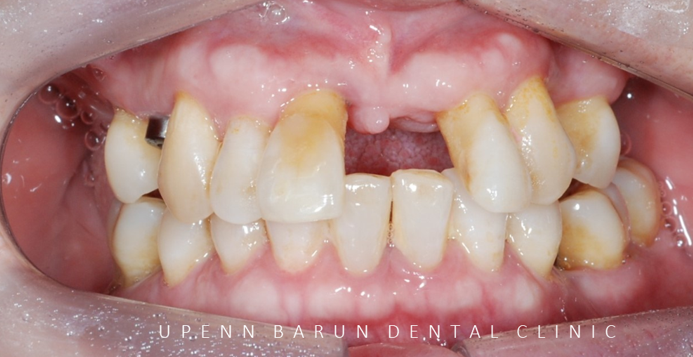

초진 정면사진

환자분께서는

현재 식사하기가 힘드신 상태로

윗니를 전체 임플란트를 하셔야 하는 상황인데다가

잠실과 해외를 왔다갔다 하시는

분이셨습니다.

내원횟수와 시간을 단축시켜 드리기 위해

전체 임플란트를 효율적으로 계획해야 했는데요 ^^

오른쪽 : 초진 파노라마

엑스레이와 함께 초진을 해보니

흔들리는 치아가 많이 있었으며

치주염으로 인해 치아들이 많이 정출되어 있었고,

어금니쪽에서 지지를 해 주지 못해

앞니끼리도 과도하게 맞물리고 있는 상태였습니다.